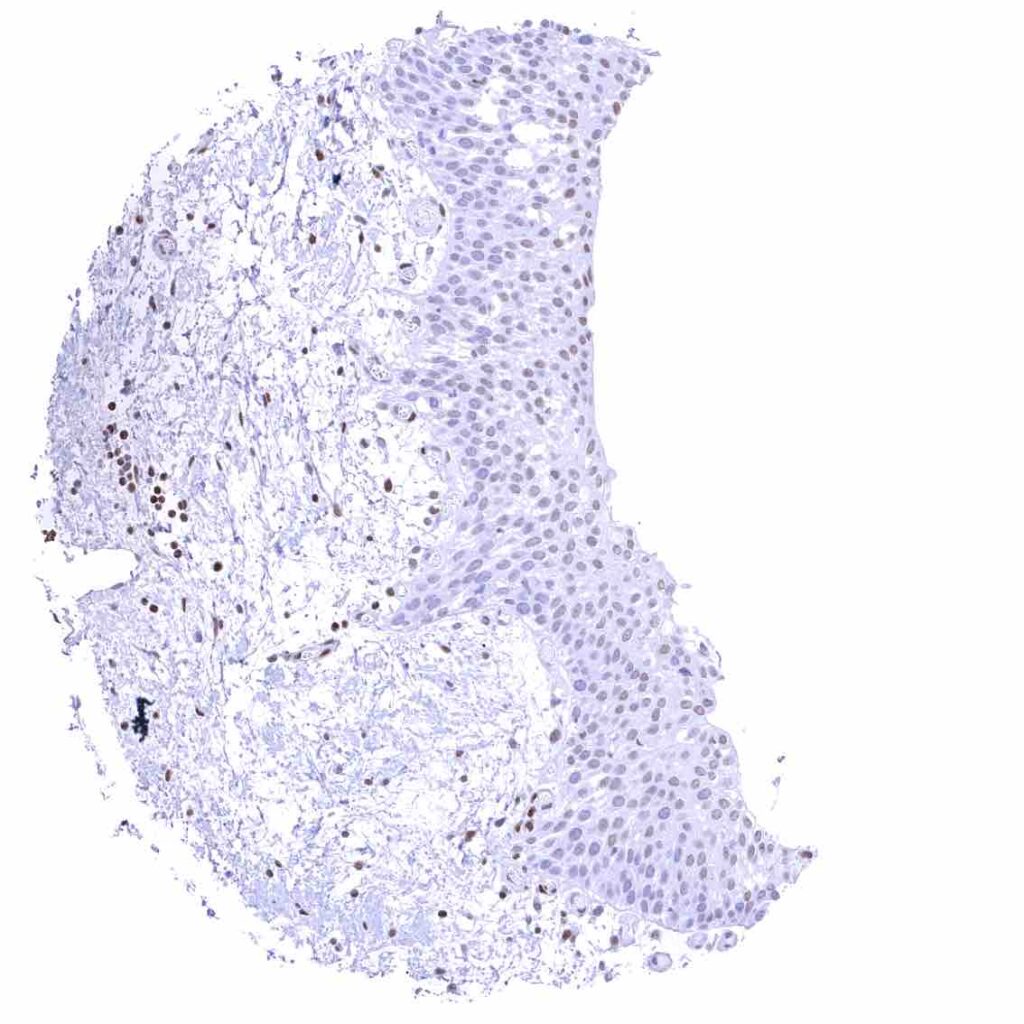

Tonsil – Strong nuclear p27 staining of a significant subset of cells, especially in the interfollicular area. Nuclear staining of squamous epithelial cells predominates in the more mature cell layers (top 50_ of the epidermis)

Tonsil, surface epithelium – Strong nuclear p27 staining of a significant subset of cells, especially in the interfollicular area. Nuclear staining of squamous epithelial cells predominates in the more mature cell layers (top 50_ of the epidermis)

Uterus, ectocervix – Nuclear staining of squamous epithelial cells predominates in the more mature cell layers (top 50_ of the epidermis).